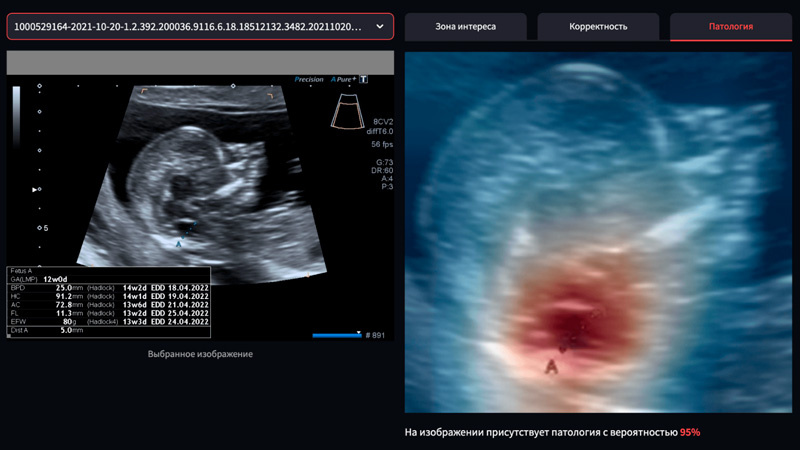

Специалисты компании Яндекс создали нейросеть, предназначенную для помощи врачам в выявлении врожденного порока развития позвоночника и спинного мозга у плода – spina bifida. Это серьезное заболевание, которое часто становится причиной инвалидности. Его сложно распознать, т. к. оно встречается примерно у одного новорожденного из тысячи. С помощью нейросети врачи смогут идентифицировать признаки заболевания на ранних сроках, что даст возможность начать дополнительную диагностику и назначить лечение.

На сайте фонда «Спина бифида», который является инициатором проекта, предоставлен бесплатный доступ к сервису. Специалисты могут загружать данные ультразвуковых исследований, проведенных в рамках первого скрининга, в систему ИИ. Нейросеть проведет анализ изображения и определит вероятность развития патологии. Это позволит своевременно направлять пациентку на дополнительные исследования в ведущие медицинские центры страны.

Ситуация с оперативной диагностикой spina bifida по-прежнему вызывает беспокойство, несмотря на значительные достижения в области медицины. Выявить данное заболевание на УЗИ в первом триместре могут только квалифицированные специалисты, хорошо разбирающиеся в особенностях болезни и анатомии плода. Чаще всего патология выявляется лишь во втором триместре, что может стать препятствием для выполнения операции в утробе матери, которая значительно улучшает прогноз для малыша.

Нейросеть обучалась на 6 тысячах уникальных обезличенных результатах ультразвуковых исследований беременных, собранных в НМИЦ им. В.И. Кулакова. Врачи центра руководили анализом всех данных и методологическими аспектами проекта. Специалисты Yandex Cloud совместно со студентами Школы анализа данных Яндекса создали систему, способную обнаруживать объекты и классифицировать их по вероятности патологии. Благодаря им сервис получил удобный пользовательский интерфейс.